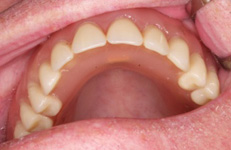

Náhrada jednoho zubu pomocí implantátu je možná také v postranním úseku chrupu. Při ztrátě většího počtu zubů ve frontálním nebo postranním úseku může být mezer uzavřena větším počtem jednotlivých implantátů.

Při ošetření pomocí jednotlivých implantátů zůstávají sousední zuby neporušené – intaktní. Při klasickém ošetření pomocí můstků musejí být tyto zuby obroušeny!